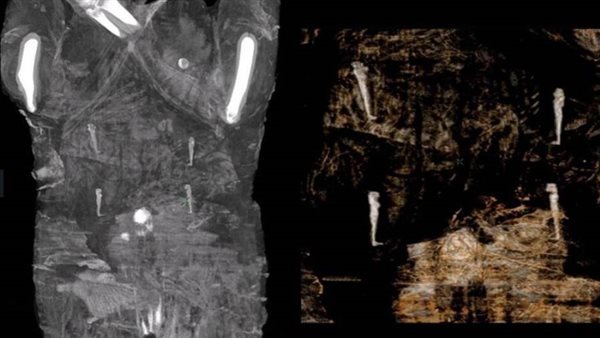

وقالت إن تلك المومياء المصرية بالمتحف الوطني البولندي والتي تم العثور عليها وهي حامل بعد اجراء اعمال فحص ودراسة لها باستخدام الأشعة المقطعية تعد (حالة نادرة). وأعربت خبيرة المومياوات عن اعتقادها بأن الوفاة في تلك الحالة حدثت بصورة مفاجئة ولذلك عملية التحنيط تمت على عجالة،لافتة الى وجود عدد من الادلة التي تكشف عن استخراج الجنين من رحم الام عند وفاتها في مصر القديمة ووضعه بجانب مومياء الأم .